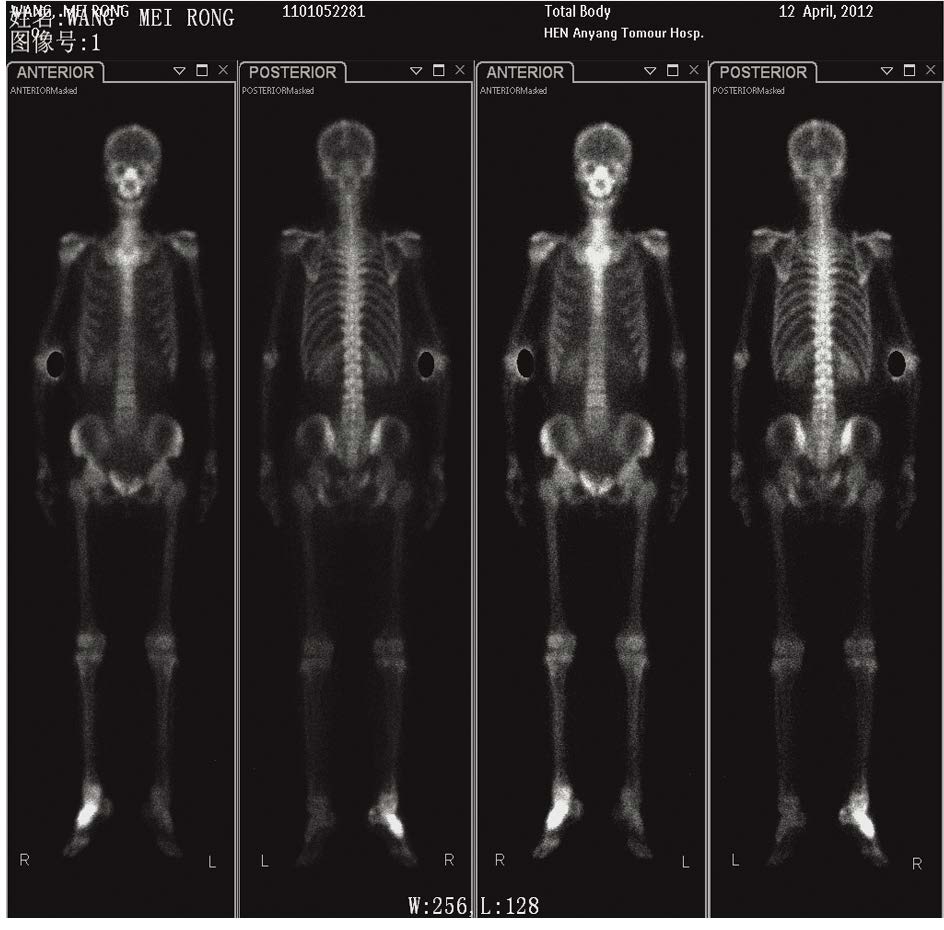

1 临床资料患者,女,49岁。主诉:月经紊乱1年,接触性阴道出血1年。妇科检查:外阴:阴毛呈女性分布,已婚已产式;阴道:通畅,黏膜光滑,穹隆消失;宫颈:结节状,直径5 cm,质糟脆,触血阳性;宫体:平位、大小正常、活动度好;附件:双侧附件区未触及异常肿物;宫旁:双侧宫旁组织结节与盆壁无间隙,弹性差。行宫颈活检辅助检查:鳞状细胞癌Ⅱ级,见图 1。彩超:右肾集合系统分离、宫颈占位、双肾积水、右侧输尿管扩张。盆腔MRI:宫颈处团块状等T1等T2信号肿物影,信号较均匀,境界不清,结合带消失。肿物侵及宫体,宫颈浆膜面模糊,肿物大小范围约4.3cm×9.0 cm。诊断:宫颈鳞癌Ⅲb期结节型。采用调强适形放疗,完成 PTV(planning target volume):DT 54 Gy/30 f,每次1.8 Gy,每周5次。放疗期间给以顺铂100 mg增敏(10 mg,静脉注射,1天1次,共10次)。行腔内后装放疗6次,A点剂量42Gy。放疗后采用PF[顺铂(50 mg/m2)+5-氟尿嘧啶(750 mg/m2)]方案全身化疗3周期。宫颈局部肿物消除满意,但治疗结束后14月出现阴道外口结节,直径2 cm。肿物活检:低分化癌。阴道转移诊断明确。行阴道结节插植放疗2次,剂量20Gy,并局部注射5-氟尿嘧啶3次,每次500 mg。采用吉西他滨+顺铂方案化疗2疗程治疗结束。15月后出现右脚肿胀、疼痛。ECT检查:全身骨骼显像清晰,结构完整,右侧足背骨可见异常放射性分布浓聚区,见图 2。核磁:右足部分跖骨、舟骨、距骨及部分根骨骨质破坏,呈长T1长T2信号改变,抑脂序列呈高信号,边界模糊,周围见软组织肿物,边界不清,关节间隙消失,见图 3。考虑右足骨转移。采用6 MV-X行右足部放疗,对穿照射,每野150 cGy/次,共10次。期间给予唑来膦酸4 mg每月1次静脉滴注,并给予恩度靶向治疗、口服药物镇痛等,疼痛较前减轻。17月后胸部CT提示:左肺下叶见数个结节影,最大者直径约0.9cm,边界清,轻度强化,考虑肺转移。采用紫杉醇+奥沙利铂方案化疗6次。从发病到死亡患者总生存期37月,骨转移后生存期22月。